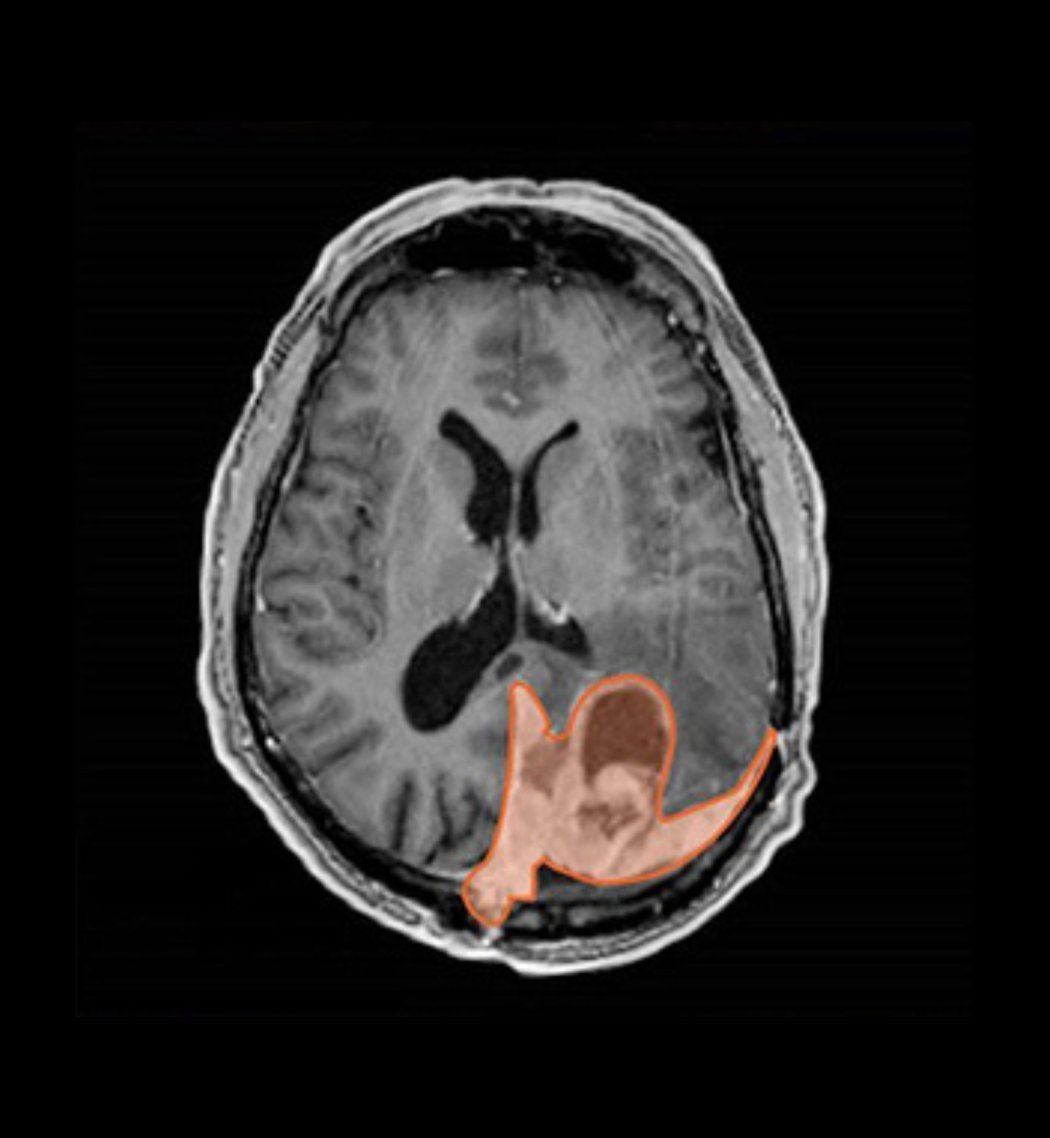

A brain tumor is usually serious. But there are different grades. About 65% to 70% of meningiomas are grade 1 tumors. These are regarded as nonmalignant and are usually surgically removed or treated with radiotherapy. If there is remaining tumor, it can also be treated with radiotherapy. Up to 95% of grade 1 patients are alive five years later, depending on age and the amount of tumor removed.

Malignant meningioma makes up about 5% of cases. These grade 3 tumors are likely to recur, and five-year survival rates are lower at about 50%.